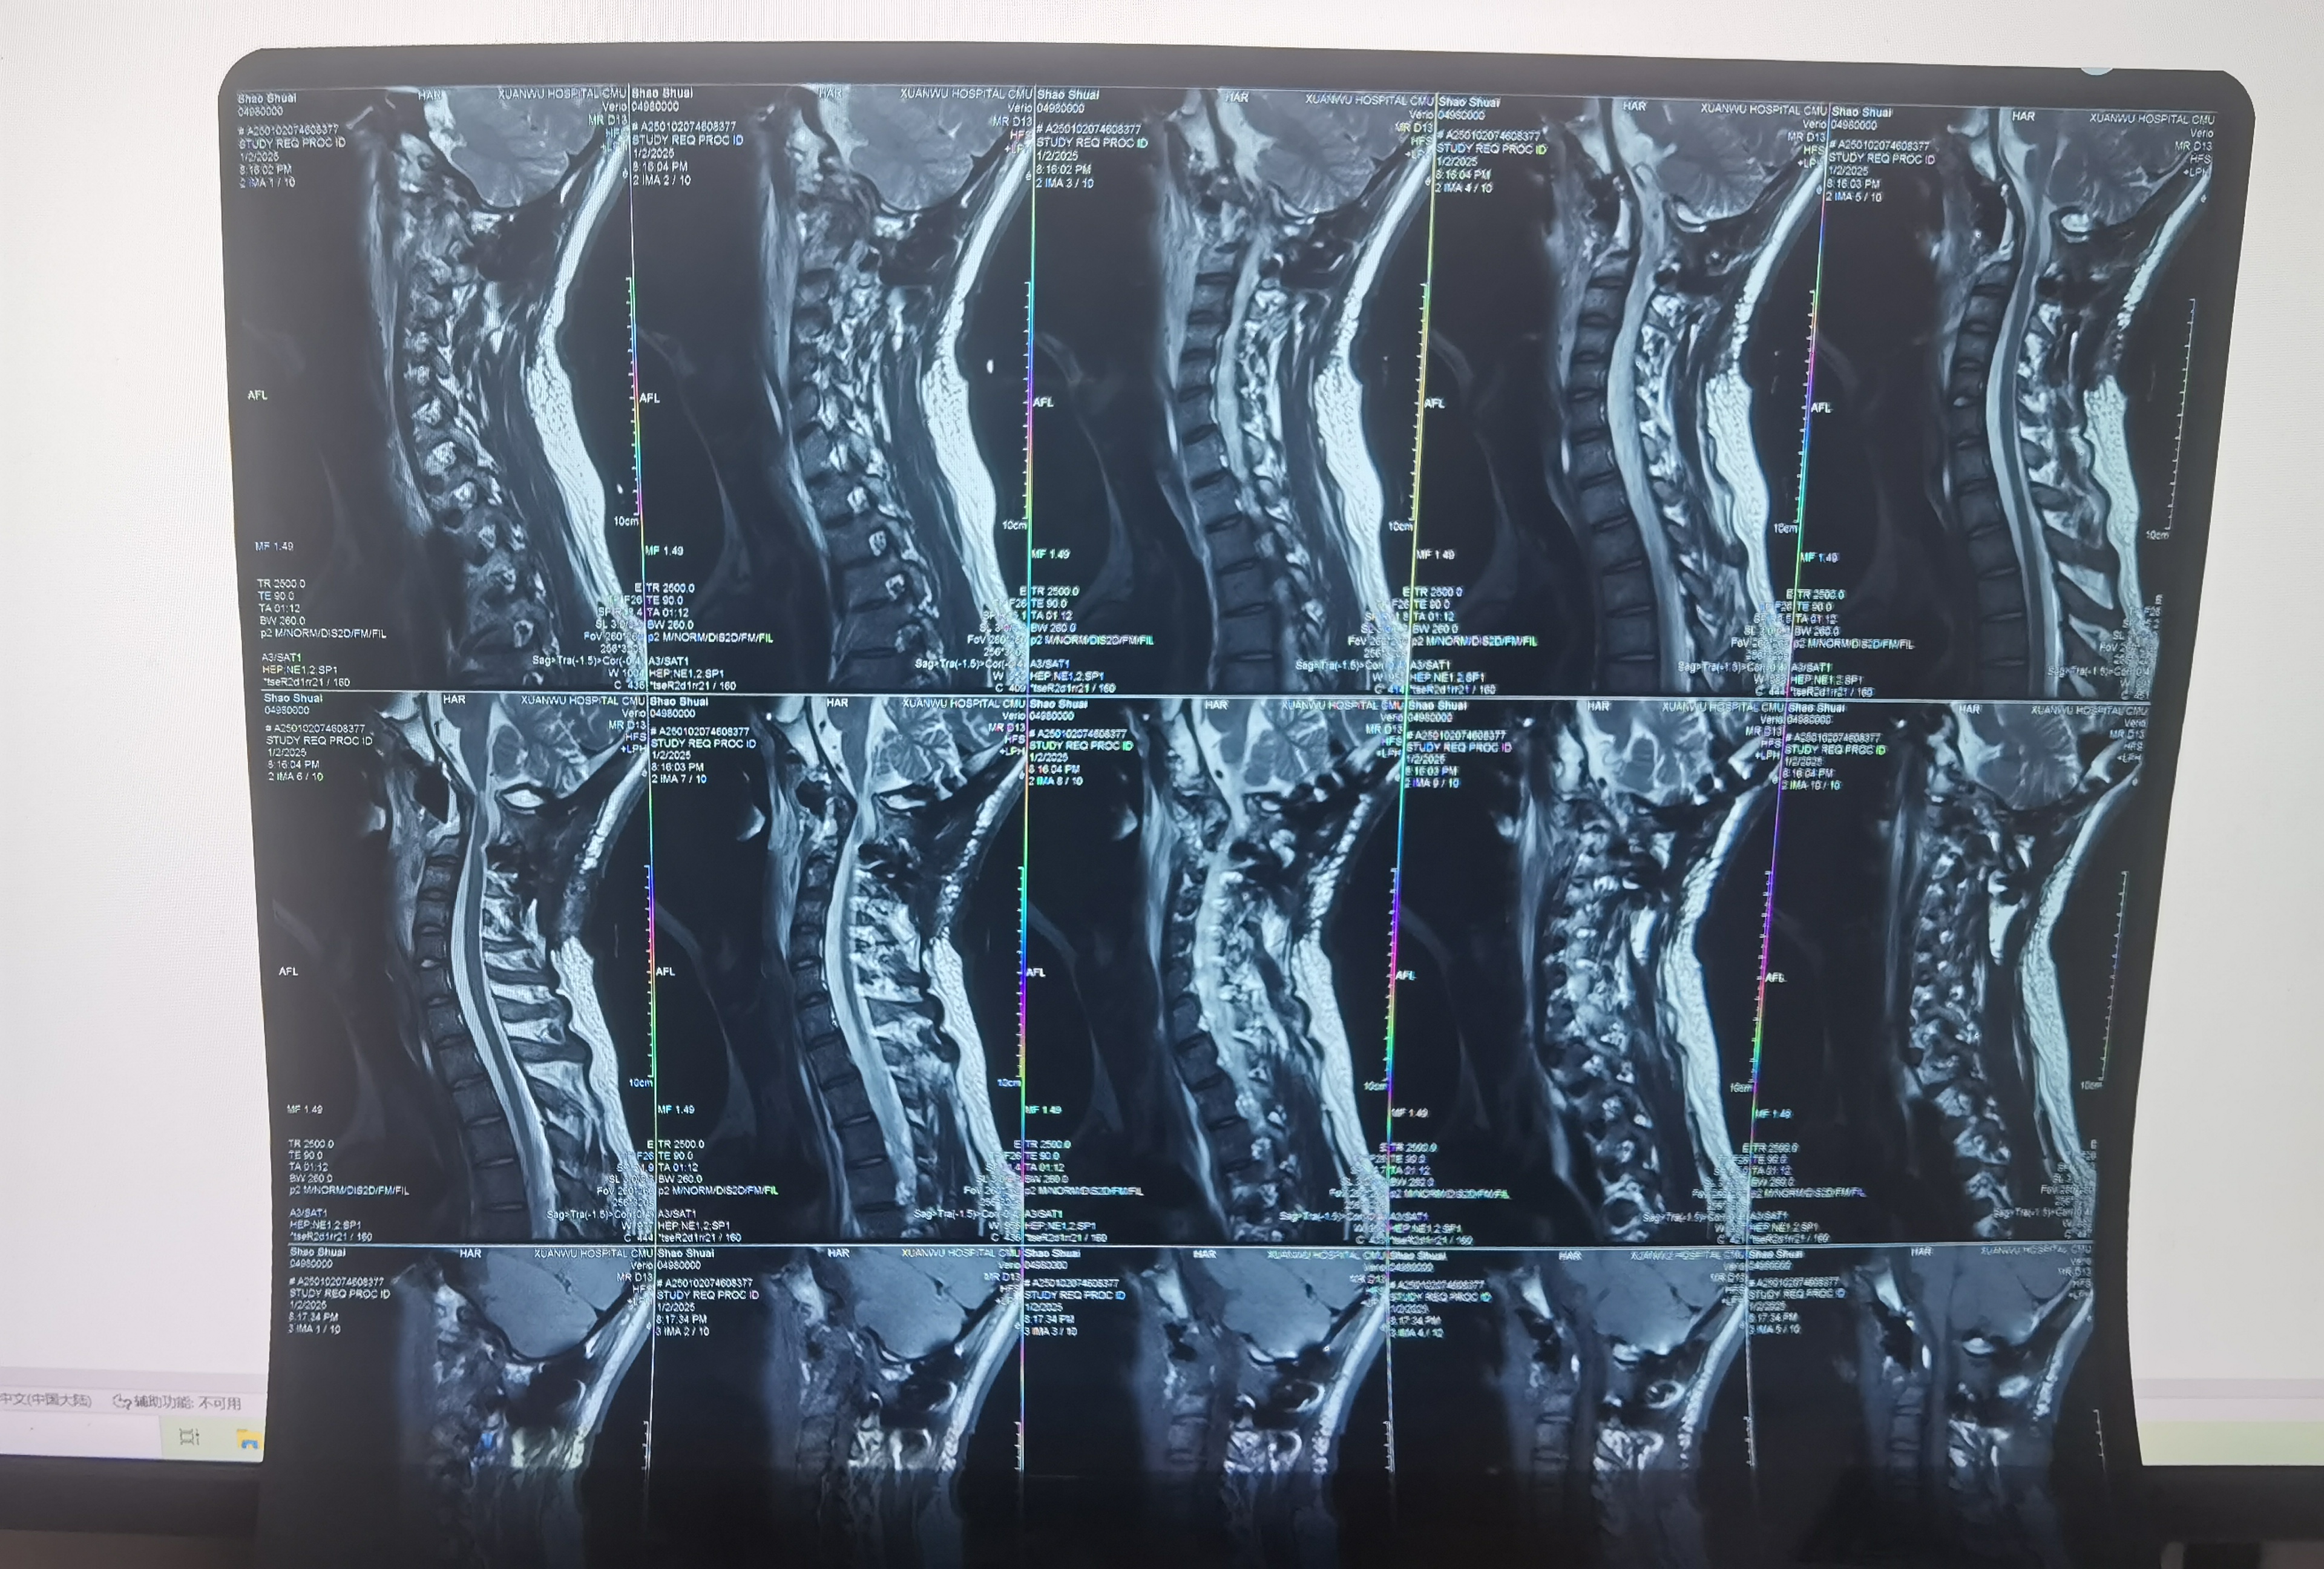

• 诊断:寰枢椎脱位

• 日期:2024.12.31

• 医院:宣武医院

• 主刀:陈赞,段婉茹一助

• 术后状况:切除齿状突,效果良好

• 术后影像: